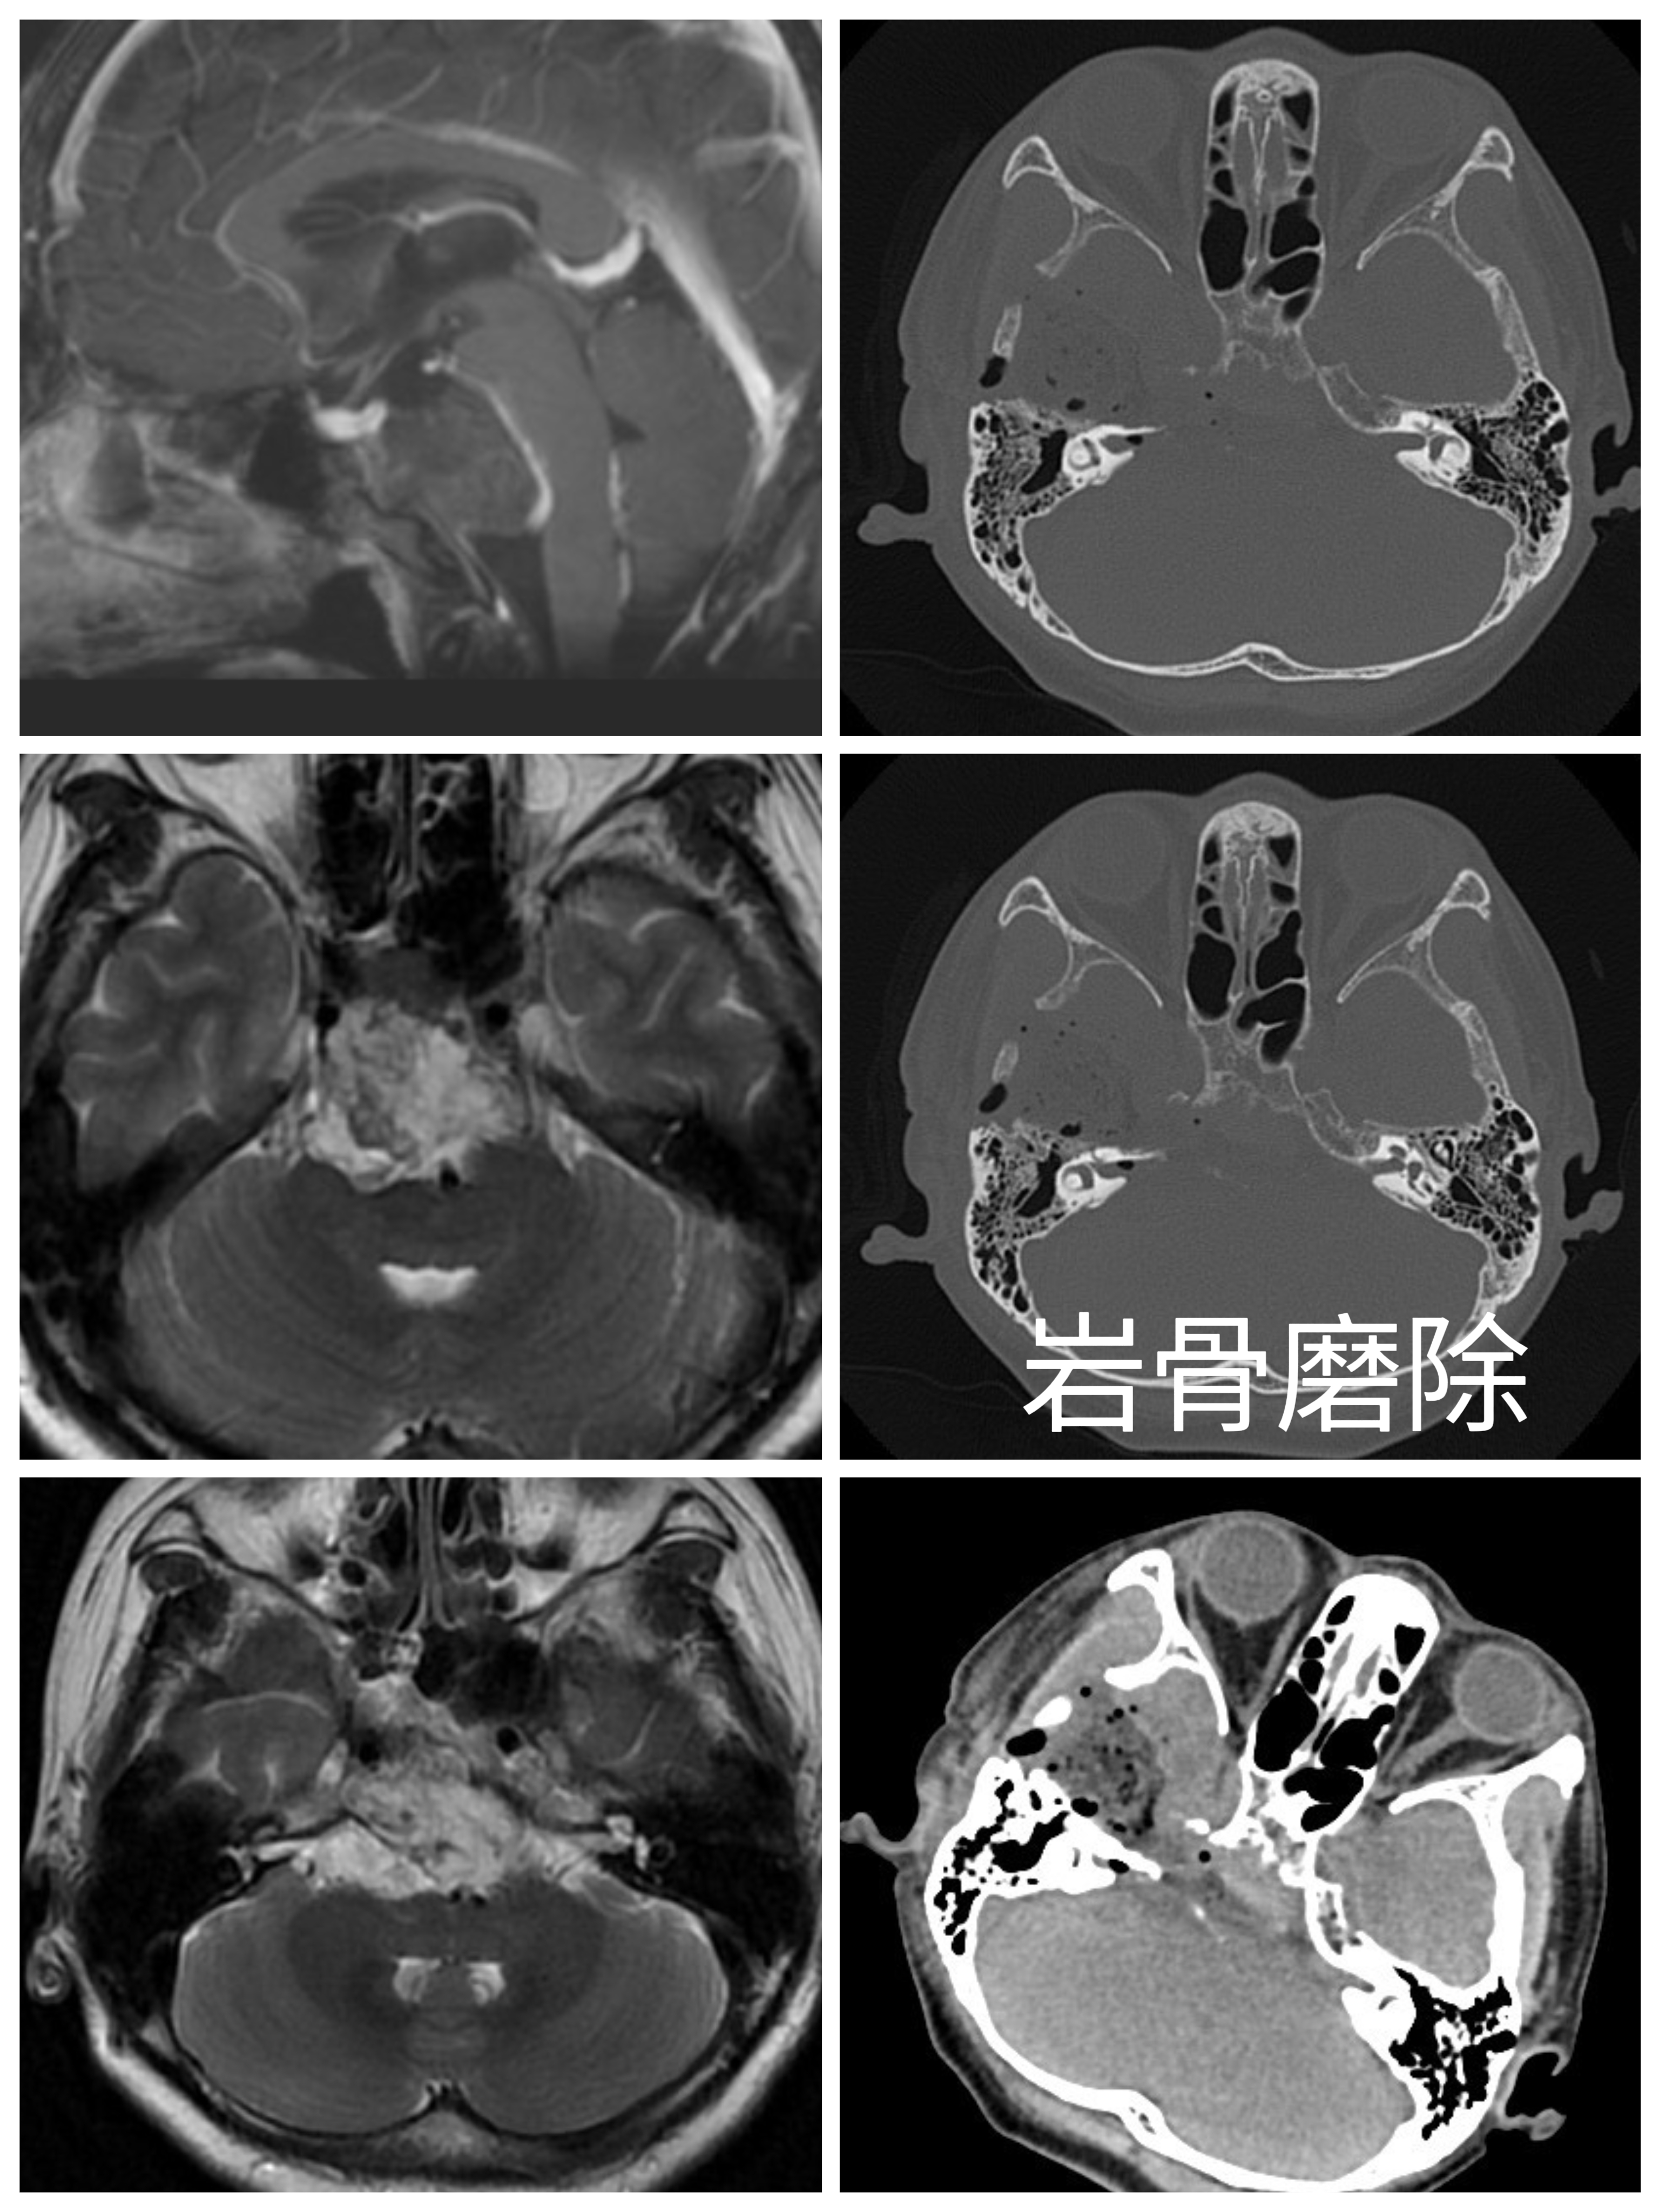

硬膜张力较高,色白,丝线悬吊骨窗硬脑膜止血。开放腰椎外引流,硬膜外抬起颞叶,予棘孔处电灼脑膜中动脉并切断。

魔钻磨除Kawase三角,见部分肿瘤位于硬膜外,肿瘤灰黑色,质软,血供丰富,使用环形刮匙和取瘤镊分块切除肿瘤,肿瘤包膜与颅底神经黏连严重,予以部分切除。弧形剪开颞部硬脑膜,脑组织博动正常。抬起颞叶,于滑车神后方切开小脑幕,电灼岩上窦,即见肿瘤,肿瘤灰红色,质软,血供一般,与双侧IV、V、VI、I、V颅神经及基底动脉粘连。显微镜下次全切除,部分肿瘤外包膜与上述神经血管黏连严重予以保留。创面电凝和速即纱压迫彻底止血。清点器械物品无误,硬膜下置引流管1 根,使用人工硬膜缝合硬脑膜,可吸收硬膜封合胶予以加固,复位并固定骨瓣,头皮和颞肌止血后,逐层缝合颞肌、帽状腱膜和头皮。